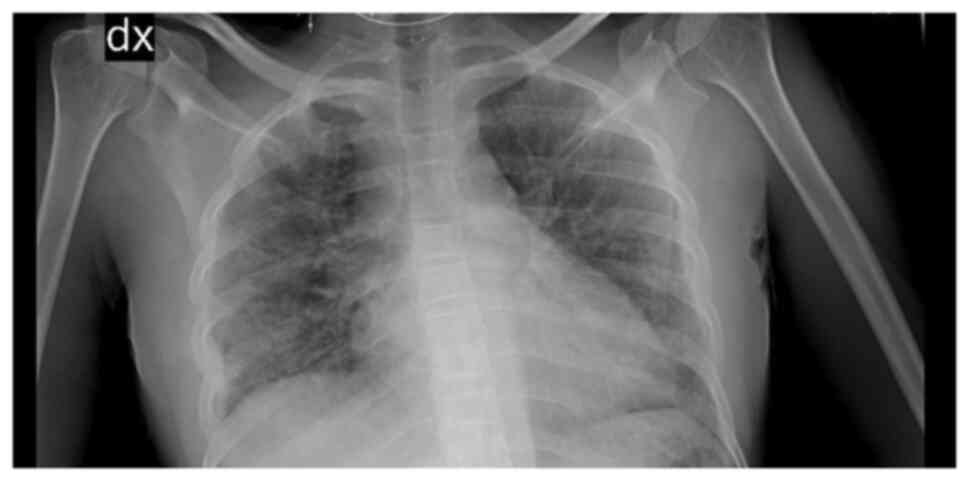

Blood tests revealed mild anaemia with a reduced red blood cell (RBC) count [haemoglobin (Hb), 9.8 g/dl; RBC, 3.34x106/mm3, normal white blood cell count (WBC), increased C-reactive protein (CRP) levels (2.38 mg/dl) along with high erythrocyte sedimentation rate levels (104 mm/h), increased total bilirubin levels (2.85 mg/dl), aspartate aminotransferase at 83 U/l and alanine aminotransferase at 56 U/l. Creatinine levels and liver function marker (coagulation and albumin) levels were normal (creatinine level, 0.56 mg/dl; international normalized ratio, 0.98; and albumin, 3.8 g/dl). Hepatitis B virus (HBV) and hepatitis C virus (HBC) along with human immunodeficiency virus (HIV) tests were negative. A chest X-ray revealed right medio-basal lung consolidation with a perivascular interstitial thickening (Fig. 1). Thorax computed tomography (CT) scan images (acquired before and after contrast administration, using a SOMATOM® Definition Flash scanner; Xenetix, 350 mg/ml; Siemens AG) revealed bilateral ground glass opacities with interlobular septal thickening, lower lobes consolidations and bilateral pleural effusion (Fig. 2), whereas an abdomen CT scan revealed homogeneous hepatomegaly, and a 3 cm densely calcified spleen (Fig. 3).

Figure 2

Thorax computed tomography scan demonstrating bilateral interstitial pneumonia along with consolidations, and bilateral pleural effusion.